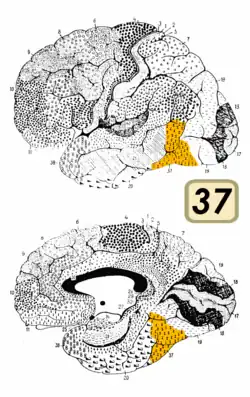

Brodmann area 37, or BA37, is part of the temporal cortex in the human brain. It contains the fusiform gyrus which in turn contains the fusiform face area, an area important for the recognition of faces.

This area is also known as occipitotemporal area 37 (H). It is a subdivision of the cytoarchitecturally defined temporal region of cerebral cortex. It is located primarily in the caudal portions of the fusiform gyrus and inferior temporal gyrus on the mediobasal and lateral surfaces at the caudal extreme of the temporal lobe. Cytoarchitecturally, it is bounded caudally by the peristriate Brodmann area 19, rostrally by the inferior temporal area 20 and middle temporal area 21, and dorsally on the lateral aspect of the hemisphere by the angular area 39 (H) (Brodmann-1909).[1]